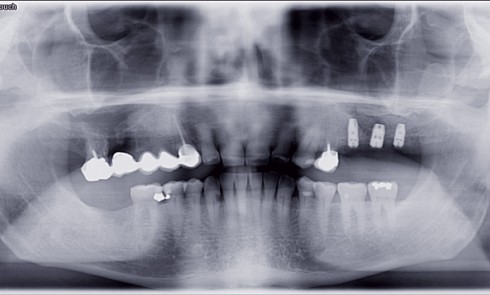

Implantologie

Article réservé à nos abonnés Comblements sinusiens. Analyse d’une situation de complication

Quelques semaines après la parution de cet article, nous recevions un message de l’unde nos confrères exposantune situation problématique consécutive...